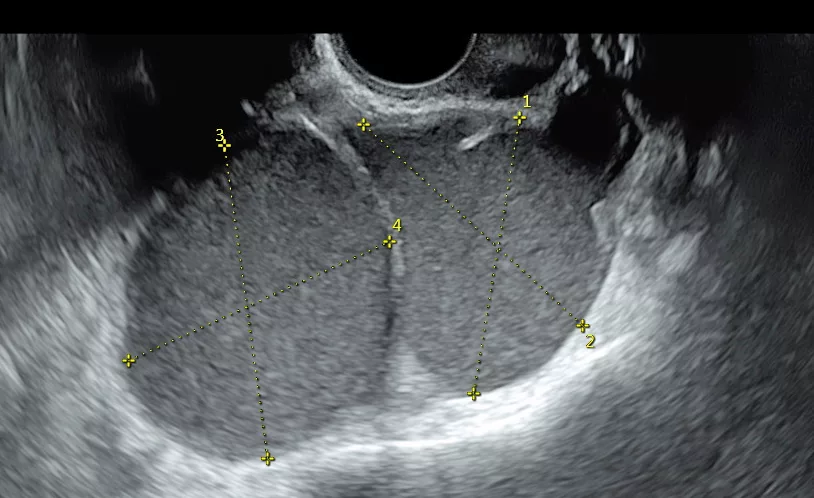

- Échographie en début de cycle (3ème – 5ème jour du cycle). Recherche des causes d’infertilité : pathologie de la cavité utérine, anomalie des trompes (hydrosalpinx), et évaluation de la réserve ovarienne avec le compte des follicule antraux (CFA).

- Échographies, dites de monitorage de l’ovulation. Étudie le nombre et la croissance des follicules ovariens et de l’épaisseur de l’endomètre dans le cadre d’un traitement de stimulation ovarienne.